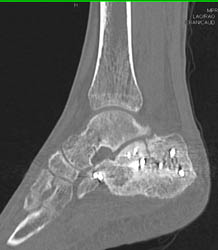

Diagnosis

Ct Angiogram of the Hand